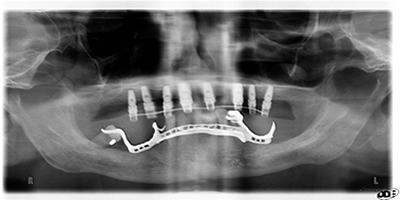

L'AMBULATORIO L'Ambulatorio Odontoiatrico Dr. Enrico Parrinello rappresenta una struttura odontoiatrica di riferimento in Sicilia occidentale. E' attrezzato per l'esecuzione di: igiene orale, cura delle malattie parodontali, estrazioni dentarie semplici, complesse o di elementi inclusi, odontoiatria conservativa, endodonzia clinica e chirurgica, sbiancamenti laser, odontoiatria estetica, impianti di filler, ortodonzia intercettiva, preventiva o di tipo fisso, protesi dentarie realizzate con tecnologia CAD/CAM e impronta digitale Cerec bluecam , ceramica metal-free, interventi implantologici flapless, interventi di implantologia osteointegratata con carico differito o immediato, implantologia multiplo elettrosaldata , studio dell'occlusione e postura in chiave kinesiologica,trattamenti osteopatici , ortopantomografia digitale, utilizzo del laser a diodi, visita con telecamera endorale. Ha ricevuto il riconoscimento di "Centro di eccellenza in implantologia" dalla Sweden & Martina, azienda leader nel settore. Eccellenza riconosciuta anche dall' Assessorato della Sanità Regione Siciliana in quanto l' Ambulatorio è stato accreditato (unico a Marsala) perché possiede i requisiti organizzativi, tecnologici, strutturali, generali e specifici. LO STAFF Il Titolare e il Direttore Sanitario dell'Ambulatorio è il Dr. Enrico Parrinello, laureato in Odontoiatria e Protesi Dentaria nel 1984 presso l' Università degli Studi di Palermo e iscritto al n. 6 dell'Albo degli Odontoiatri di Trapani. Dal 1984 al 1986 ha posto le basi della propria professione presso un centro odontoiatrico di Palermo operante con il SSN. Dal 1986 è libero professionista a Marsala. Nel 1990 è convenzionato esterno con l' USL n.3 ed è Professore di Odontostomatologia presso la scuola Infermieri Professionali dell' Ospedale S. Biagio di Marsala. Dal 1991 esegue interventi di implantologia osteointegrata. Utilizza gli impianti Calcitek e Pitt-easy, quindi inizia la collaborazione con la Sweden & Martina utilizzando gli impianti New Tech, Stark, Premium e Kohno. Ha completato il suo iter implantologico con il carico immediato con le tecniche flapless e implantologia multiplo elettrosaldata . Dal 1995 collabora con il centro Orthocheck II di Napoli e si occupa personalmente del trattamento ortodontico dei propri pazienti utilizzando la tecnica bidimensionale del Prof. Giannelly della Boston University. Nel 1996 apre un secondo studio a Petralia Soprana e nel 1997 un terzo a Gangi dove opera fino al 2001. Nel 2000, dopo aver acquistato il locale, il Dr. Parrinello si trasferisce nella attuale sede e la trasforma negli anni in una struttura odontoiatrica di eccellenza. É C.T.U e C.T.P.. E' socio SIO , Società Italiana di Implantologia Osteointegrata . Partecipa periodicamente a corsi e congressi nazionali ed internazionali riguardanti l' osteointegrazione ed è stato invitato come relatore in corsi di aggiornamento. Nell 'Ambulatorio si occupa di: implantologia, chirurgia, ortodonzia, protesi, laser, filler, odontoiatria estetica. La Dr.ssa Roberta Alagna si è laureata in Odontoiatria e Protesi Dentaria nel 2004 presso l' Università degli Studi di Siena ed è iscritta al n. 306 dell' Albo degli Odontoiatri di Trapani. Ha partecipato a Master in endodonzia clinica e chirurgica diretti da Castellucci e Malagnino. Nell' Ambulatorio si occupa di: endodonzia clinica e chirurgica, odontoiatria conservativa, igiene orale e prevenzione, sbiancamenti laser, parodontologia, pedodonzia. La Sig.ra M. Patrizia Angileri, ragioniere e perito commerciale, ha partecipato a corsi di formazione di operatore office, grafico web ed è rappresentante dei Lavoratori per la sicurezza nell' area odontoiatrica. Nell' Ambulatorio si occupa dell'area segreteria/refertazione .